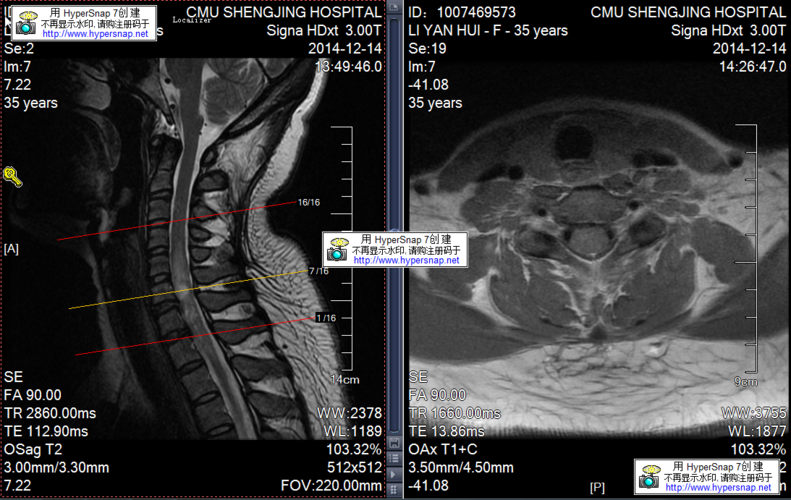

反复发作的脊髓脱髓鞘病变一例

脱髓鞘核磁共振图

脱髓鞘病变症状

脱髓鞘疾病

脱髓鞘改变